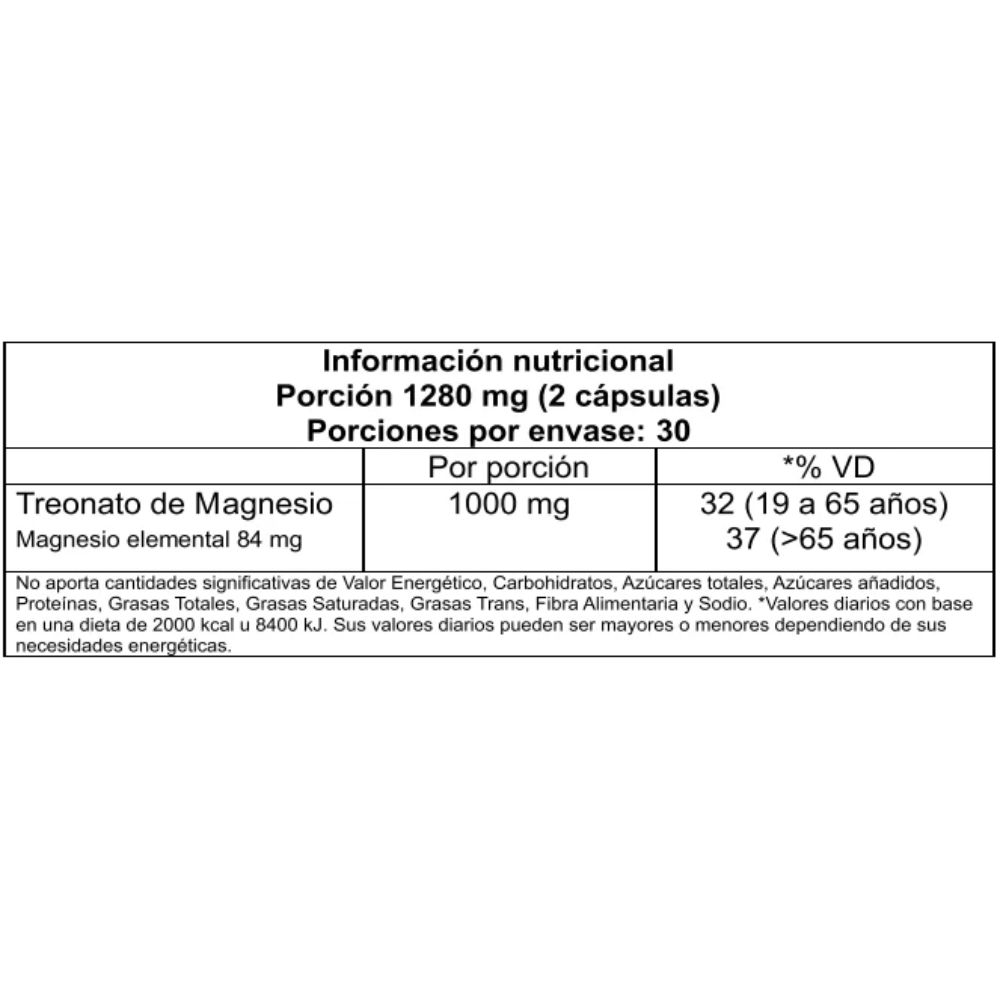

Treonato de Magnesio 60c Vitatech

Envase con 60 cápsulas

Magnesio (como L-treonato de magnesio)

Consumir 2 cápsulas diarias, preferentemente con las comidas o según indicación de un profesional de la salud.